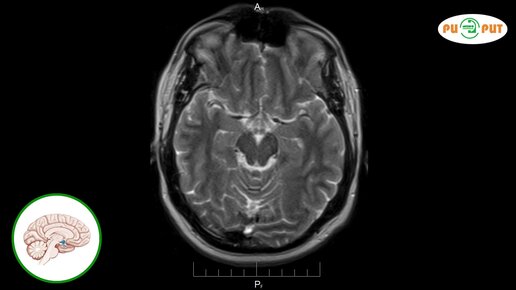

Что видно на МРТ гипофиза с контрастом (видео)